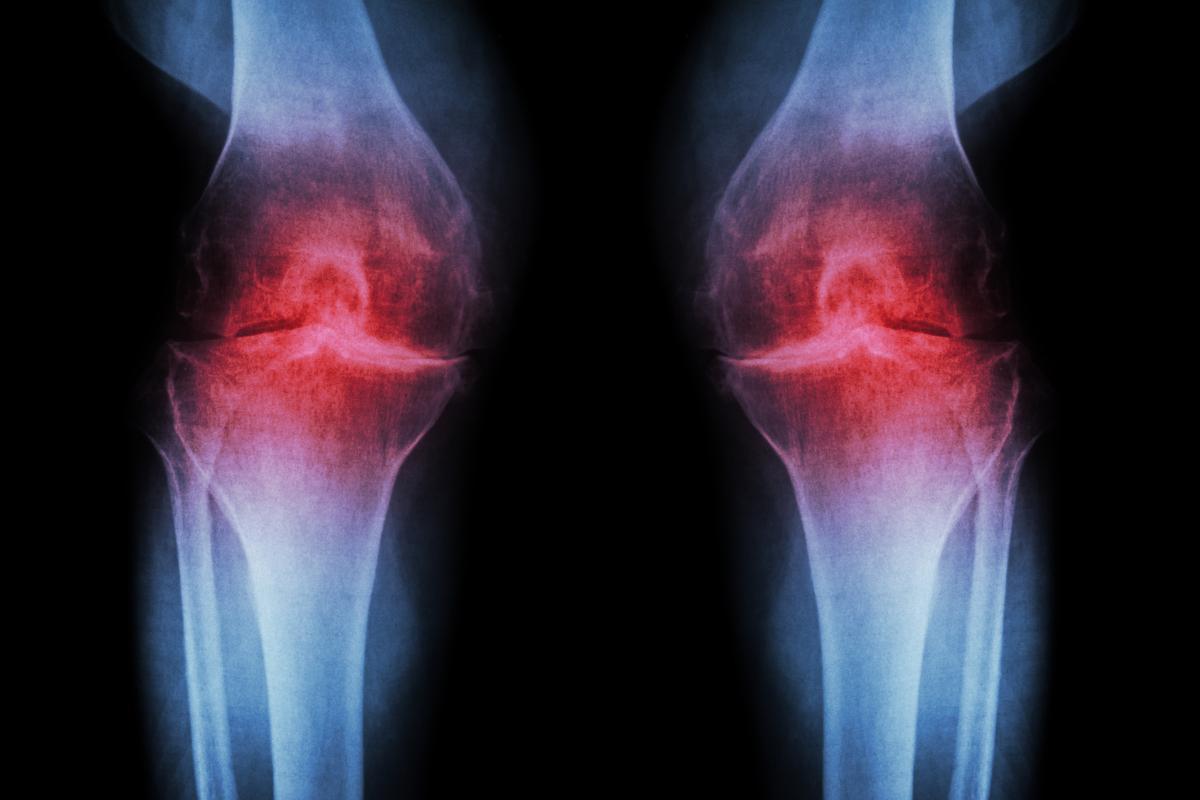

Artrose

Se você está se perguntando por que o seu cachorro grita de dor do nada, mesmo que ninguém o toque, é importante saber que as patologias das articulações, especialmente a artrose, são processos que acabam desgastando as articulações. Isso faz com que o osso subjacente fique exposto, levando o organismo do cachorro a compensar criando mais osso ao redor da articulação para reduzir a mobilidade e aliviar a dor causada pelo atrito entre as extremidades. Esse processo traz consigo um grande problema, pois a musculatura se modifica e outras articulações podem ser sobrecarregadas, resultando em um desequilíbrio de cargas que gera dor, que às vezes pode ser maior do que a dor da própria artrose.

A artrose pode afetar cachorros de qualquer raça, mas é mais comum em cães mais velhos. Para saber mais sobre como identificar e tratar a artrose, consulte o seguinte artigo: "Artrose em cães - Sintomas e tratamento".

Artrite

Outra doença dolorosa que pode fazer com que os cachorros se queixem é a artrite, que consiste em uma inflamação das articulações que afeta cães de todas as idades. Trata-se de um processo inflamatório das camadas protetoras que revestem as articulações, levando os cães afetados a apresentarem dor, perda de mobilidade e rigidez nas articulações.

Assim como a artrose, a artrite é uma doença degenerativa que não melhora com o tempo e, na verdade, piora. Nessa doença, os ossos acabam provocando atrito uns nos outros devido à perda de cartilagem nas articulações. A artrite pode ser causada por traumas, infecções, fatores genéticos, resposta imunológica ao ataque do próprio sistema imunológico do cachorro à membrana sinovial e até mesmo pelo excesso de peso e obesidade. Confira nosso artigo sobre "Artrite em cachorros - Sinais clínicos e tratamento".